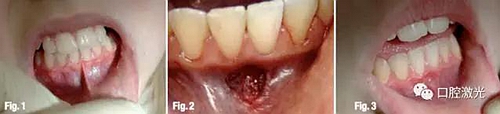

案例3 兒童下唇系帶

9歲兒童下唇系帶過短,實施表麻后利用鉺激光進(jìn)行切割延長處理。圖三是術(shù)后8天后恢復(fù)狀況。

案例5 種植體二期

28歲男性患者,實施表麻后通過鉺激光進(jìn)行牙齦切除,從而暴露種植體。圖三是治療15天后的狀況。